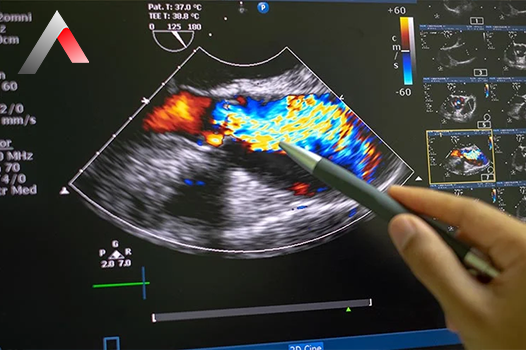

EKO, ekokardiyografinin kısaltmasıdır ve kalbin yapısını ve fonksiyonunu değerlendirmek için kullanılan bir görüntüleme testidir. Bu testte, ses dalgaları kullanılarak kalbin hareketli bir görüntüsü oluşturulur. EKO, kalp kapakçıklarının durumunu, kalp kasının pompalama gücünü, kalp odacıklarının boyutunu ve diğer kalp fonksiyonlarını değerlendirmek için kullanılabilir.

EKO, kalbin yapısını ve fonksiyonunu değerlendirmek için kullanılan bir görüntüleme testidir. Bu testte, ses dalgaları kullanılarak kalbin hareketli bir görüntüsü oluşturulur. EKO, kalp hakkında detaylı bilgi sağlayan ağrısız ve güvenli bir testtir.

• Doppler ekokardiyografi: Kalbinizdeki kan akışının hızını ve yönünü ölçer.